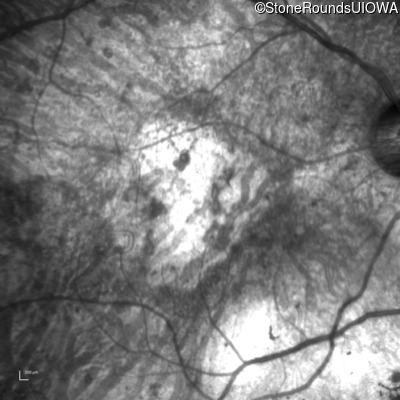

OD

OS

1/200 sc

Age at visit:

76 years